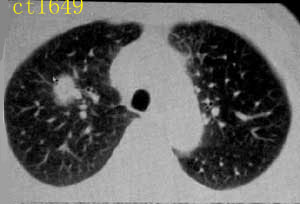

ct1649:guzhongliangddd提供 胸部腺癌

http://www.radida.com/radinet/read.php?tid=4865